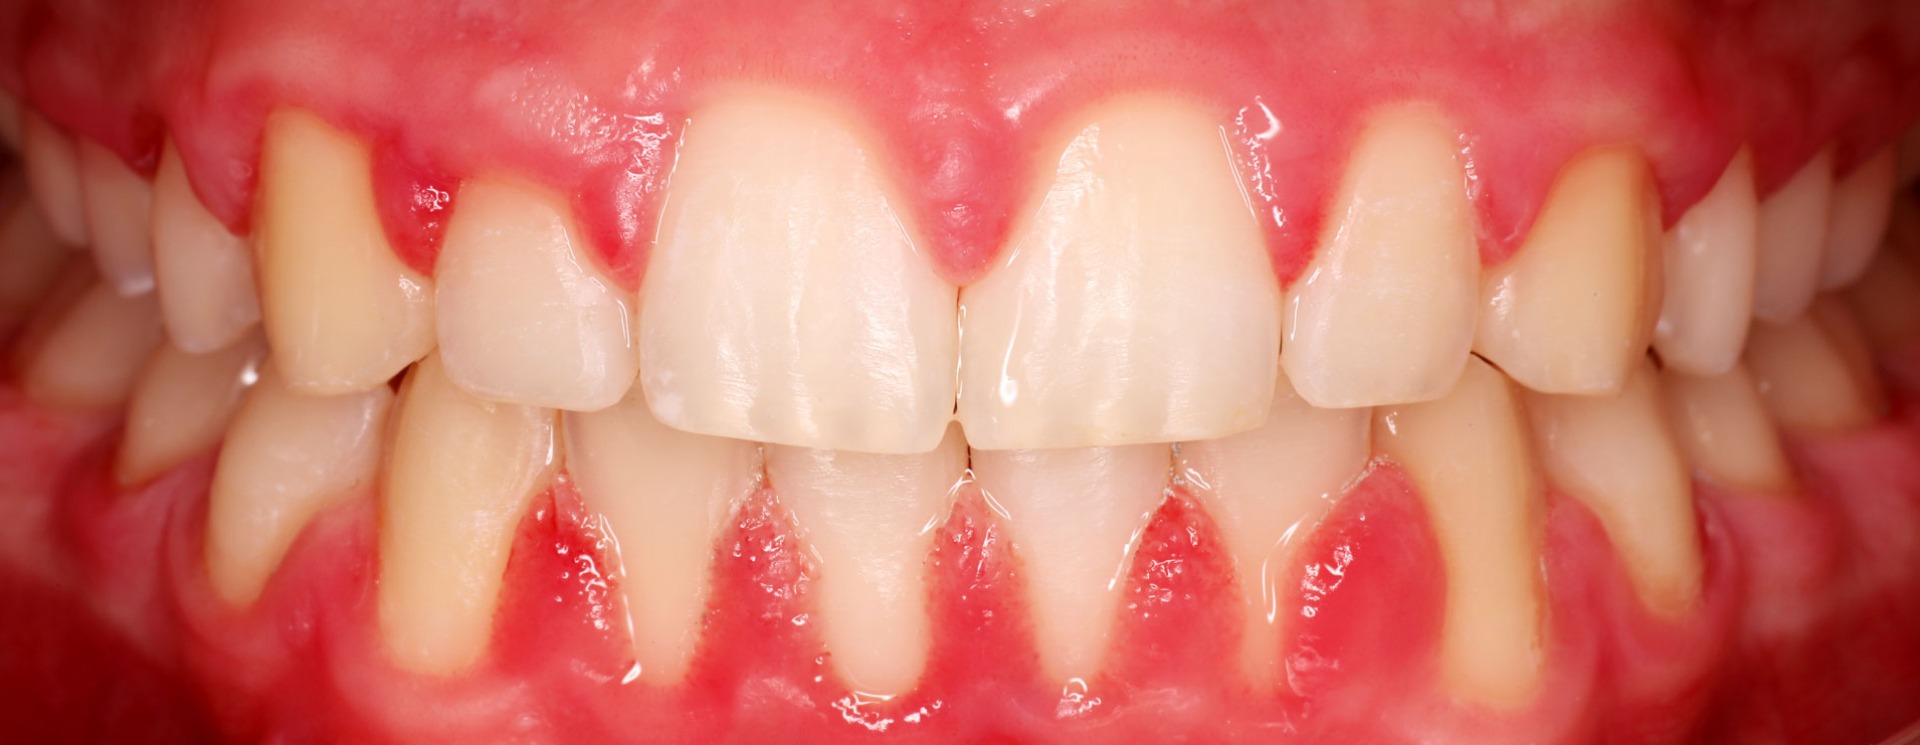

Periodontite

Progressão inflamatória da doença periodontal que leva à destruição dos restantes tecidos de suporte dos dentes: o ligamento periodontal (conjunto de fibras que existem entre os dentes e o osso maxilar) e o osso que suporta os dentes.